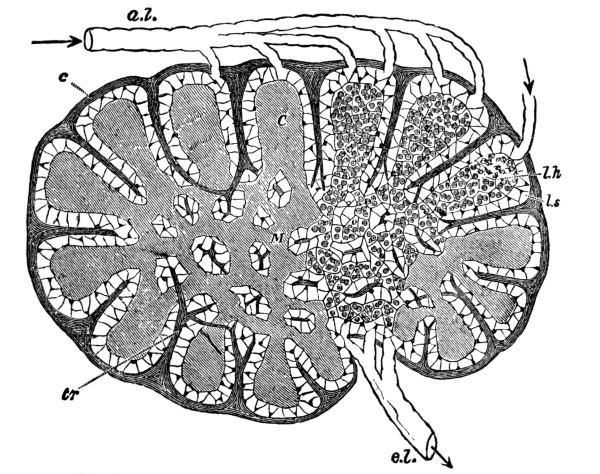

Fig. 8.—Diagram of a lymphatic gland, showing afferent (a. l.) and efferent (e. l.) lymphatic vessels; cortical substance (C); medullary substance (M); fibrous coat (c); sending trabeculæ (tr) into the substance of the gland, where they branch, and in the medullary part form a reticulum; the trabeculæ are surrounded by the lymph path or sinus (l. s.), which separates them from the adenoid tissue (l. h.). (Sharpey.)

The lymphatic glands are small oval glandular bodies and occur here and there along the course of the lymphatics. Before entering one of them the vessel breaks up into several afferent vessels which form a plexus within and then emerge again as several efferent vessels which soon unite to form one trunk. These glands occur chiefly in the mesentery, along the great vessels, and in the mediastinum, axilla, neck, elbow, groin, and popliteal space.

The lymph varies in character with the locality, being a little thicker and more opalescent in the lacteals, as the lymphatics of the [Pg 33] small intestine are called, especially during digestion, when fat is present. Here it is called chyle. Otherwise it is generally a clear, transparent and slightly opalescent fluid, which, owing to the presence of fibrin, clots when drawn from the body and allowed to stand. In fact, it resembles blood plasma very closely in composition and, as it also contains a certain number of corpuscles or leucocytes that just correspond to the white corpuscles of the blood, it is practically blood without the red corpuscles. These leucocytes have considerable power of amœboid movement and are thought by some to play an important part in the absorption of food.

The lymph glands serve as a protection to adjacent parts and when it leaves the gland the lymph is purer and richer in leucocytes than when it entered. In fact, they filter harmful matter from the lymph and apparently also form white corpuscles. Normally they can with difficulty be felt, but in disease, if the leucocytes are unable to destroy or carry off the poison, the lymph carries it along to the glands, which swell and become tender. If the infection is not severe the swelling goes down and the tenderness passes after a short time, but if it is severe, there may be suppuration and abscess formation and [Pg 35] the gland even perhaps be destroyed, giving its life for the health of the part. Thus a wound in the foot, if infected, may cause irritation and enlargement of the glands at the knee and in the groin.